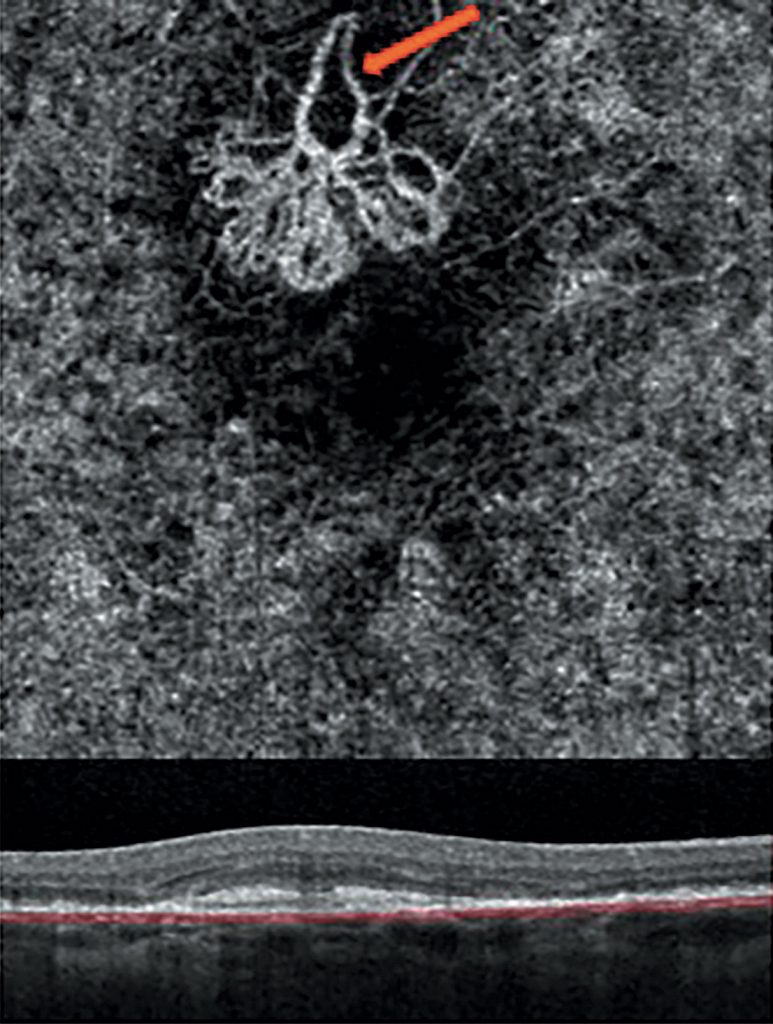

Die OCT-Angiografie lässt sich als Standarduntersuchung ver-gleichbar der bisherigen OCT-Untersuchung zur Diagnostik ver-schiedener Erkrankungen des Hinterabschnitts einfach anwen-den. OCT-Untersuchungen zeigen jedoch in neuerer Zeit, dass im Bereich des Quellpunktes unter der subretinalen Flüssigkeit umschriebene, „okkulte“ PEA variabler Größe nachweisbar sind (Abb. 7), sodass die oben genannte Aufteilung wohl revidiert werden muss.

OCT Angiografie Die OCT-Angiographie (OCT-A) ist eine neue Methode zur Darstellung durchbluteter Netzhaut- und Aderhautgefäße ohne Gabe eines Kontrastmittels – mit den entsprechenden Risiken und Nebenwirkungen. Sie

OCT-Angiographie in Deutschland: Präsentation, Nomenklatur und Zukunftswünsche Stand Januar 2017 Die OCT-Angiographie (OCT-A) ist eine neue nicht-invasive diagnostische Methode, die eine differenzierte Darstellung der retinalen und in geringerem Ausmaß der chorioidalen Gefäße sowohl im gesunden als auch im erkrankten Zustand ermöglicht (1-4).

Eine aktive Form der feuchten Makuladegeneration ist durch eine Fluoreszenz-Angiographie nachweisbar. Bei dieser Untersuchung wird die dynamische Verteilung der Flüssigkeiten in der Netzhaut aufgezeigt. OCT-Angiographie (OCT-A) Eine OCT-Angiographie stellt rein durch Bildgebung und ohne Farbstoffinjektion Netzhaut- und Aderhautgefäße dar. Die durchbluteten Gefäßsysteme werden durch eine spezielle Aufnahmetechnik hochauflösend und dreidimensional in verschiedenen Netzhautschichten sichtbar gemacht.

OCT-Angiographie Diese neue Technologie ermöglicht die Darstellung retinaler Blutgefäße ohne die intravenöse Injektion von Farbstoffen. Dies ist insbesondere hilfreich, um Durchblutungsstörungen oder pathologische Blutgefäße darzustellen. Réalisez votre examen OCT angiographie které jsou cévně zásobené dokáže au Centre: diagnostic non invasif des maladies rétiniennes (DMLA, diabète, occlusions vasculaires). Die OCT-Angiographie (i) des hyperfluoreszenten Bereichs (s. gestrichelter Kasten in h) zeigt eine fein verästelte sekundäre choroidale Neovaskularisationen (CNV)

Hintergrund: Die OCT-Angiographie (OCT-A) ermöglicht eine detaillierte Betrachtung der Binnenstruktur von choroidalen Neovaskularisationen (CNV), im Gegensatz zur Fluoreszenzangiographie (FAG), bei der durch die Gefäßleckage die Struktur der Gefäße überstrahlt wird. Die OCT begann mit der Time-Domain -Technik (TD-OCT) und wechselte zur schnelleren Anwendung der Spektral-Domain-OCT (SD-OCT) oder Swept-Source -OCT (SS-OCT) (Abb. 12.1). Die neue OCT-Angiographie Hintergrund Die OCT (OCT-A)-Methode wird seit 2015 entwickelt und bietet eine nicht-invasive Angiographie der retinalen und chorioretinalen Gefäße (Abb. 12. • OCT-Angiographie bei OCT-A bei anderen Makulopathien und Glaukom In jedem Block wird zur Einführung ein kurzes Übersichtsreferat gehalten, um danach an Hand von Fällen und einem Panel eine strukturierte Diskussion über die Rolle und Interpretation der OCT-Angiographie unter Einbeziehung des Auditoriums zu starten.